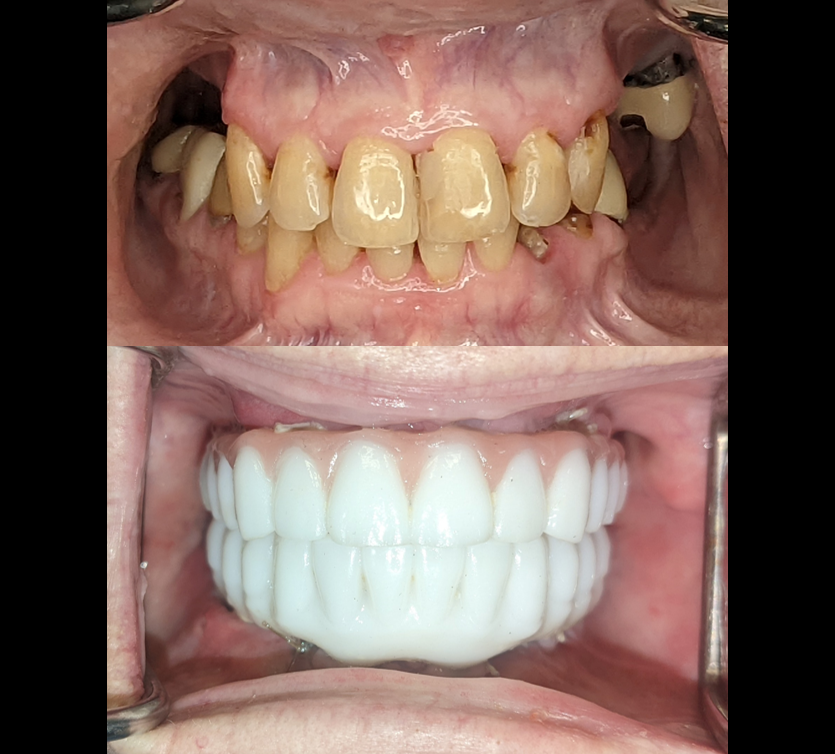

Smile in one day for our lovely patient! Dual arch PFAST case. Recurrent caries, non-restorable terminal dentition.

3D facially driven restorations using Instarisa facial scanner and micron mapper. Prosthesis printed using Einstein 3D printer and double arch delivered same day with little to no adjustment on occlusion.